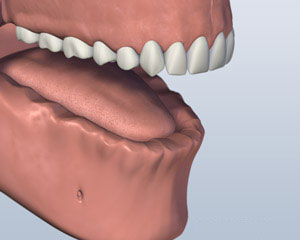

1. 之前

1. 之前

1. 之前

1. 之前